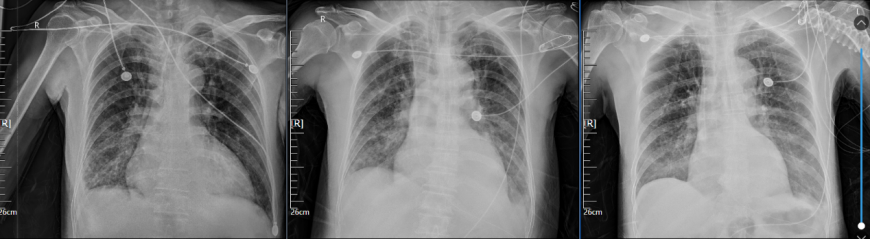

患者治疗期间床旁胸片变化见图4。

图片

4  患者床旁胸片变化情况

注:从左到右依次为10月7日、10月13日、10月17日床旁胸片。